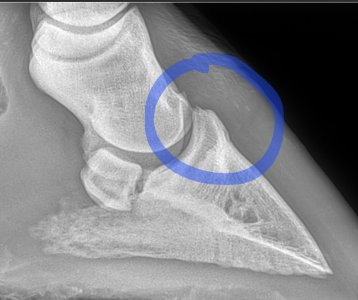

We are going to confer in Monday to see how he is with a view to her coming back if not sound. Options are possible coffin joint arthritis although I'd asked her if she thought it was this before when she came out initially to xray and she said she felt the xray wasn't bad enough for it to be this. Xray attached.

Second photo heel area.

I'm not sure I'd be happy with this area here B. That channel looks like it narrows and also looks like it's forcing the joint apart further back. I'm no expert at xrays though. Ludo and Charlie below for comparison I'm sorry Lari is continuing to cause you worries.

What I'm struggling with, is that the vet who took the xrays did not make any comment about the area ringed in ycbm post. If I were you @Birker2020 I would see if you can get the xrays reviewed by another vet, and in particular question them about the highlighted area.

That first xray the circle area is too close together

May 23 to March 25, the difference is very clear. Sorry B, even if that isn't the cause of the current lameness you've got a definite issue there. I would personally be particularly worried about how and why the joint is being pushed apart in the middle.

Not from what I can see and from what I see on other x rays of good joints. The joint space shouldn't, I don't think, have got bigger in the middle like that and the culprit looks like arthritis at the front, commonly called low ringbone.